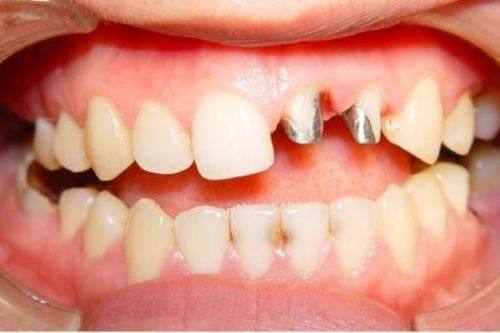

虽然烤瓷牙有特别多优点,但也存在一些不足之处。其中一个问题是美观可能会受影响。因为烤瓷牙的金属基底,可能会导致牙龈边缘透出灰线,尤其是在笑起来或者张嘴的时候,就会比较明显,这对于一些对美观要求较高的患者来说,可能就不太能接受。

部分患者还可能面临过敏风险。有些患者对金属过敏,在安装烤瓷牙后,可能会出现牙龈红肿的情况,不仅影响美观,还会让口腔产生不适感。